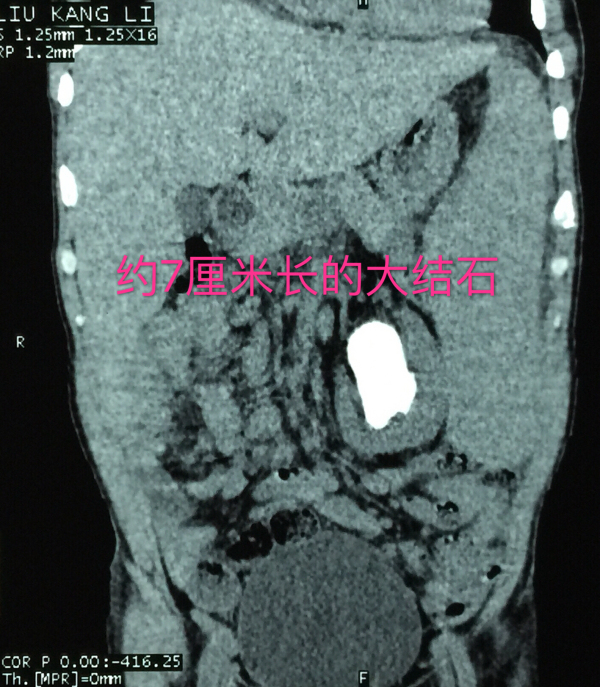

老刘白细胞149.59×10^9/L,右侧中上腹部有畸胎瘤占位,左肾结石非常巨大且复杂,而左肾又被白血病形成的巨大脾脏紧密包绕,还不包括胸膜和里三层外三层的肠道,从老刘的左肾取出结石无异于伸手从火红的熔铁炉内取出石头!要在老刘的身上做手术,将有80%的危险性,若不积极治疗,病人将面临100%的危险!

先密切监测血象、中西医结合降白细胞,输血改善贫血状况……等老刘的身体稳定后,经患者家属同意,11月16日梁泰生主任采取了目前国内外没见报道过的方法为老刘进行手术,即在全麻下行腹腔镜联合左侧经皮肾镜碎石取石术,经过3个多小时的努力,手术获得成功,术后老刘安返病房。

在老刘住院期间,泌尿外科的医生和护士众志成城,细心监护,一共请血液科、肿瘤科等科室专家进行了16次会诊,为他进行15次输血,2次抢救……虽然过程艰辛且曲折,但最终,泌尿外科的医护人员和老刘一起战胜了病魔,获得了成功,术后的老刘精神状态变得很好,白细胞值接近正常值,术后复查X光片显示结石被清理得很干净!12月10日,老刘顺利康复出院。出院当天,老刘一家还执意要和梁泰生主任合影留念以表感谢。